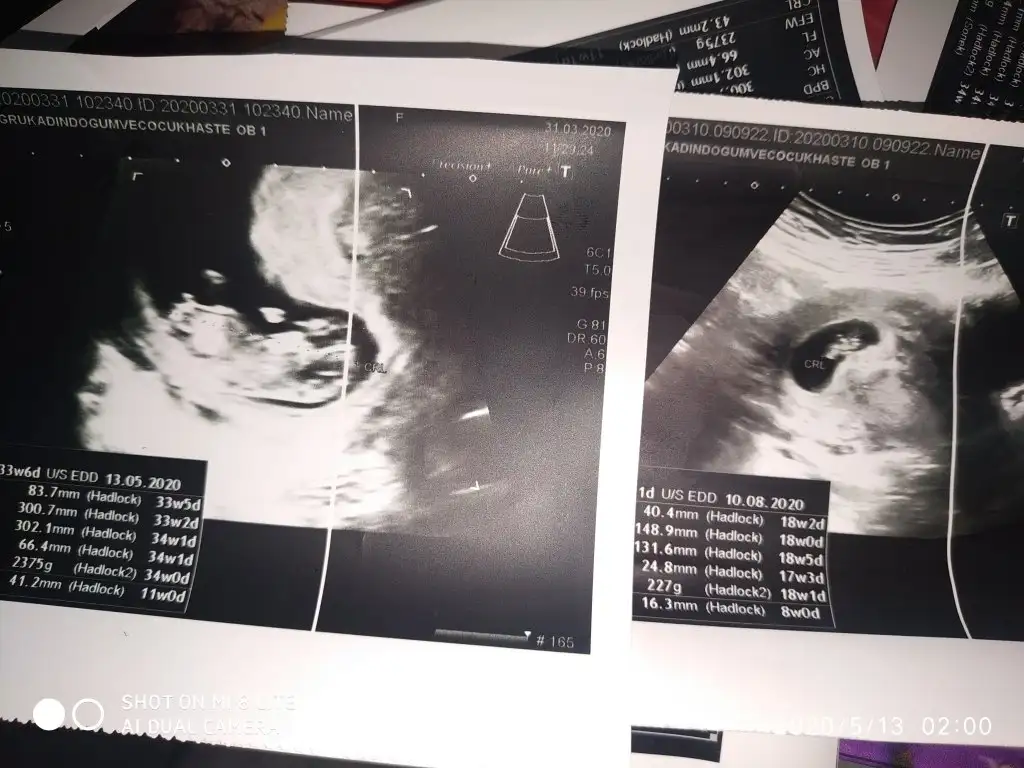

Birincisi 7+4ikincisi 5+3 bakalım bende tutacakmı benim 2 kızım var gönülden erkek geçiyor ama önce sağlıklı olması tabi henüz öğrenemedim öğrenince yazacam burdan